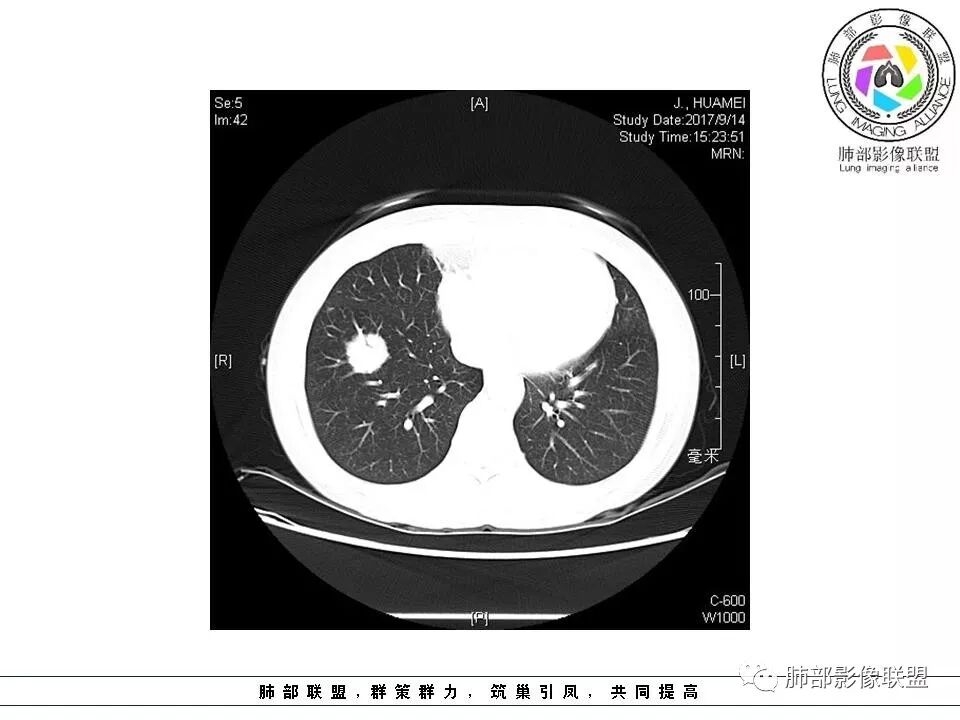

患者中年女性,因“体检发现右下肺占位4天。”入院,肿瘤标记物NSE轻高。

胸CT:右肺下叶前基底段占位性病变,内可见支气管穿过,病灶边缘不规则,呈浅分叶,未见明显毛刺。纵隔窗可见病灶密度相对均匀,增强可见病灶强化,内可见血管增粗,边缘模糊,总体考虑恶性,腺?。良性疾病鉴别错构。

南边老师分析

这个病灶边缘还是有一点点恶性征象,有分叶,似乎有点地方还有一些小毛刺样感觉

部分区域整体以膨隆为主,部分区域稍收缩

内部支气管走形非常自然,达远端稍扩张;内部血管穿行也非常自然

内部密度比较均匀,我们一般来说,首先良性肿瘤不支持,因为它里面的血管走形太自然了;然后就是炎性病变跟恶性肿瘤,但是它的边缘膨隆比较厉害,有些地方还毛刺,不是很清楚,倾向一个恶性病变

恶性的血管穿行自然,包括支气管稍扩张,最常见还是淋巴瘤,它强化比较均匀;

粘液腺癌一般支气管扩张比较罕见,这个密度及强化太均匀,不是很符合,所以把淋巴瘤放前面,癌待排;

方向定在恶性的,炎性病变不是很符合